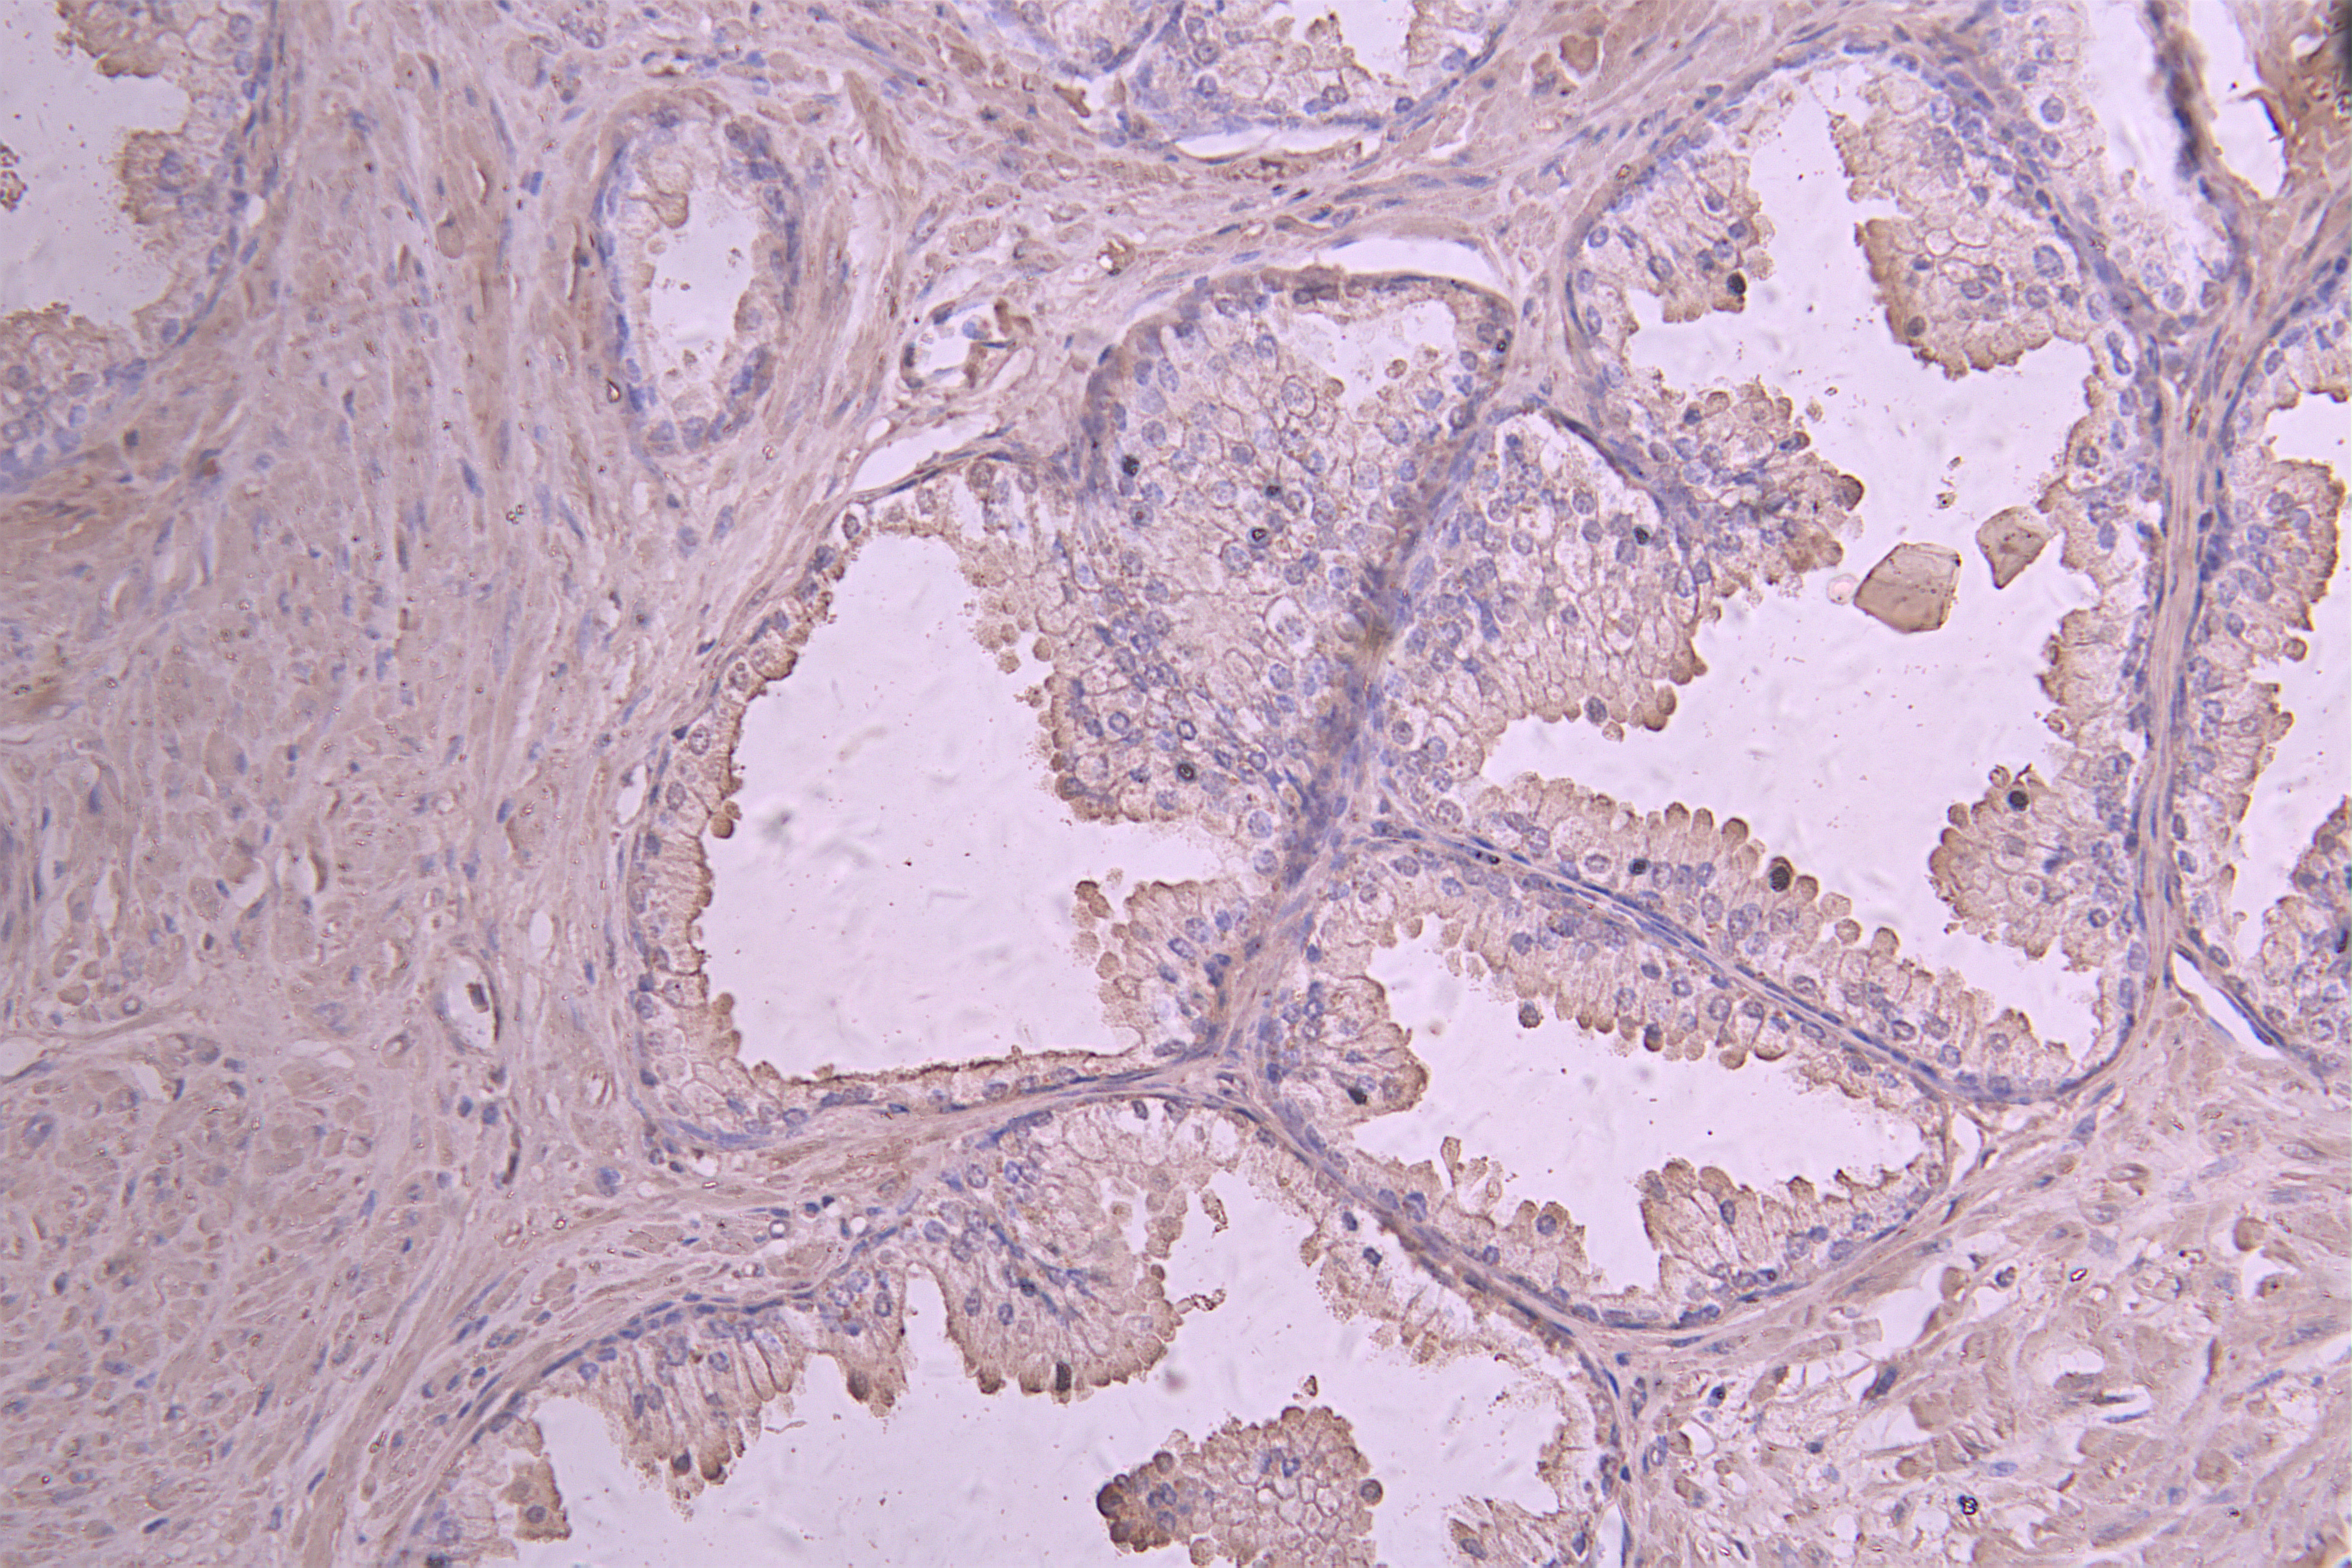

• IHC image of CSB-RA011586MA1HU diluted at 1:50 and staining in paraffin-embedded human prostate cancer performed on a Leica BondTM system. After dewaxing and hydration, antigen retrieval was mediated by high pressure in a citrate buffer (pH 6.0). Section was blocked with 10% normal goat serum 30min at RT. Then primary antibody (1% BSA) was incubated at 4°C overnight. The primary is detected by a Goat anti-human polymer IgG labeled by HRP and visualized using 0.05% DAB.